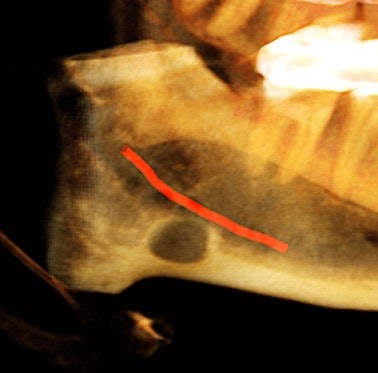

Figure 4: Coronal view of the posterior right mandible (the inferior alveolar canal highlighted in red) and 3D-reconstructed image of the posterior right mandible.

There is a hypodense lesion (radiolucent) that is well-defined, well-corticated, oval in shape, 8 x 6 mm, located at the posterior right mandible, and distal to tooth #32. The lesion is located below the inferior alveolar canal. No expansion is observed in the cross-sectional views. No calcifications are observed inside the lesion.

The majority of cases are located in the posterior mandible, between the mandibular angle and first mandibular molars and below the inferior alveolar canal. They are asymptomatic, with a slightly predilection for men between 50 and 70 years old. The diagnosis is incidental, since patients do not usually present with clinical symptoms.

From the radiographic perspective, Stafne bone defects are radiolucent lesions, well-defined and well-corticated, oval in shape, and located below the inferior alveolar canal. No expansion is usually observed in the coronal views.

The differential diagnosis includes benign and malignant lesions; however, the location below the inferior alveolar canal is an anatomical landmark that helps to differentiate a Stafne bone defect from odontogenic lesions (usually located above the inferior alveolar canal).